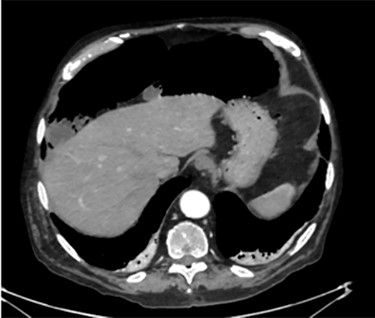

PCI was ultimately identified retrospectively using lung window settings.

PCI first documented by Du Vernoy in 1783 [4] refers to the intraoperative or radiological findings of intramural gas-filled cysts in the bowel wall (Fig. 4). PCI can easily mimic pneumoperitoneum on radiological imaging as CT, being a very sensitive examination, may show even minimal circumferential gas collections outside the bowel lumen or misrepresent some findings [5]. Liu et al. [6] found that PCI was misdiagnosed as a surgical abdomen in up to 27% of cases resulting in unnecessary operation. It is important to differentiate idiopathic PCI with a secondary form of this condition known as pneumatosis intestinalis which is not in fact a disease but a rare finding characterized by the presence of gas in the submucosal and/or subserosal of the bowel wall that may result from an underlying pathological process (Table 2). PCI has a reported incidence in general population of 0.03% on autopsy series and up to 0.37% in CT series. Its prevalence is still unknown [7]. However, Adachi et al. [8] in a retrospective, single-center study found 24.7% of PCI cases in the selected group affected by pneumoperitoneum. PCI involves most commonly the small and large bowel (respectively 42% and 36% of cases; in 22% is concomitantly present), but could also involve the mesentery and omentum [7]. Physiopathology remains still unclear although some hypotheses have been proposed such as: the ‘mechanical theory’ where an increased pressure of intraluminal gas secondary to mechanical problems breach the mucosal or serosal layers (i.e. blunt trauma, persistent vomiting, ileus or endoscopy); the ‘bacterial theory’ where an excess of intraluminal bacterial production of nitrogen gas diffuse through the bowel wall; the ‘chemical theory’ where malnutrition can prevent the digestion of carbohydrates and increased bacterial fermentation in the intestine; the ‘pulmonary theory’ that refers to increased intraluminal bowel pressure due to the respiratory system [9].